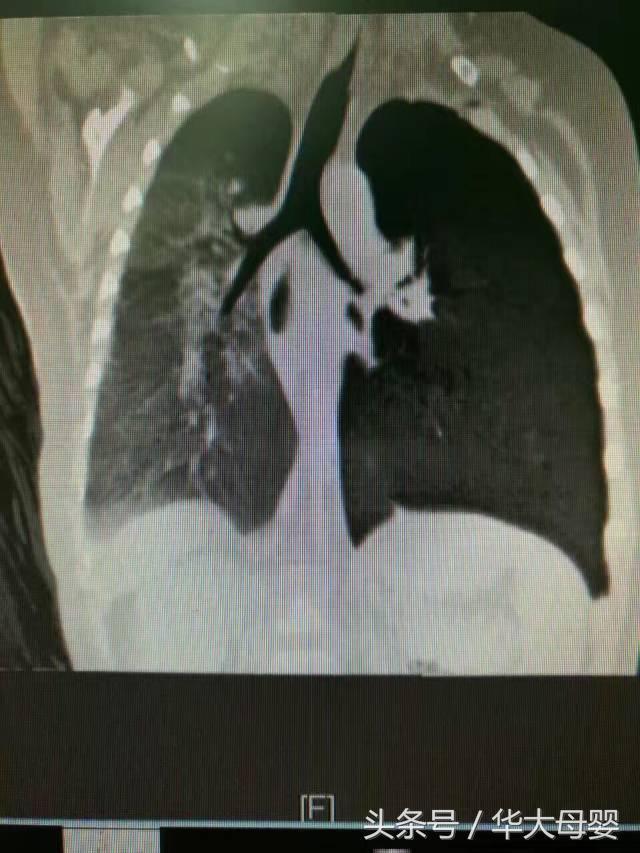

他在朋友圈說:9個月的寶寶反覆肺炎3個月,CT提示支氣管異物纖維支氣管鏡下見異物,位於左下葉基底段:

嘗試夾取異物未成功,轉我科支氣管硬鏡取出2mm大小的藍色塑料珠,懷疑為衣服裝飾物。